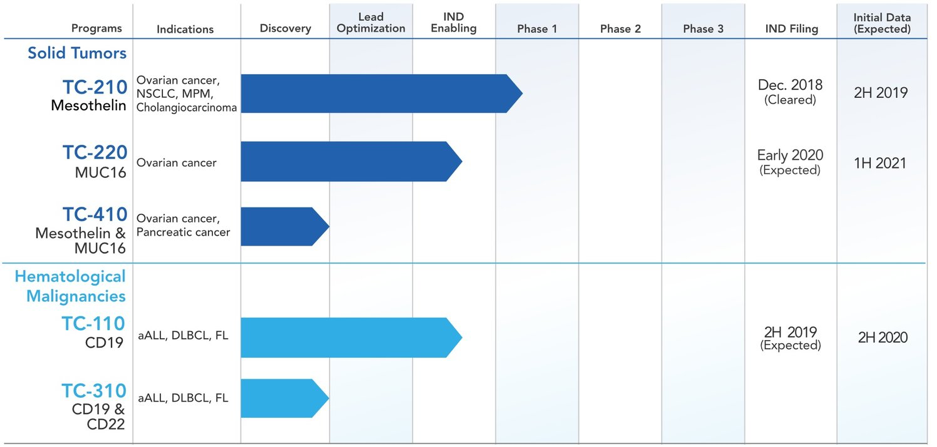

The company’s lead drug candidate TC-210 was granted an Investigational New Drug (IND) status by the FDA in January 2019. Preparations are underway for a phase I/II Clinical trials to be initiated in Q1, 2019. Its pipeline has an impressive line-up of drug candidates targeting multiple conditions such as ovarian cancer, pancreatic cancer and hematological malignancies.

Image Source: https://www.tcr2.com/our-approach